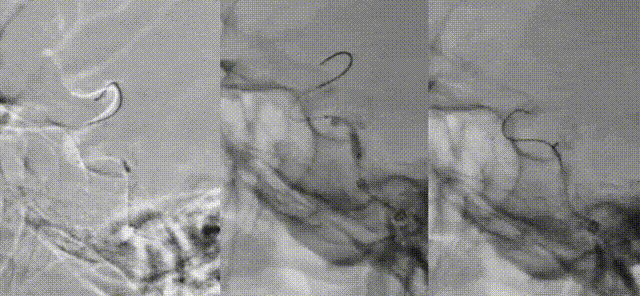

Zenith Distal Access Catheter was advanced to the cavernous segment of the right ICA. A 2m microwire and an Echelon-10 microcatheter were used to navigate through the occluded ophthalmic segment to the M1 segment of the right MCA. The Echelon-10 was then exchanged for a Transend™ 300 microwire.

Sequential angioplasty of the ICA was performed using a 2.0 mm × 15 mm balloon catheter, followed by a 3.0 mm × 15 mm balloon catheter. Post-dilation angiography demonstrated improved flow through the cavernous segment.

Stenting was performed by advancing a 3.0 mm × 20 mm intracranial drug-eluting stent and a 4.0 mm × 15 mm Resolute Integrity RX stent to the stenotic segment over the Transend™ 300 wire. Both stents were successfully deployed under roadmap guidance, with angiography showing improved luminal diameter and residual stenosis of approximately 20%.